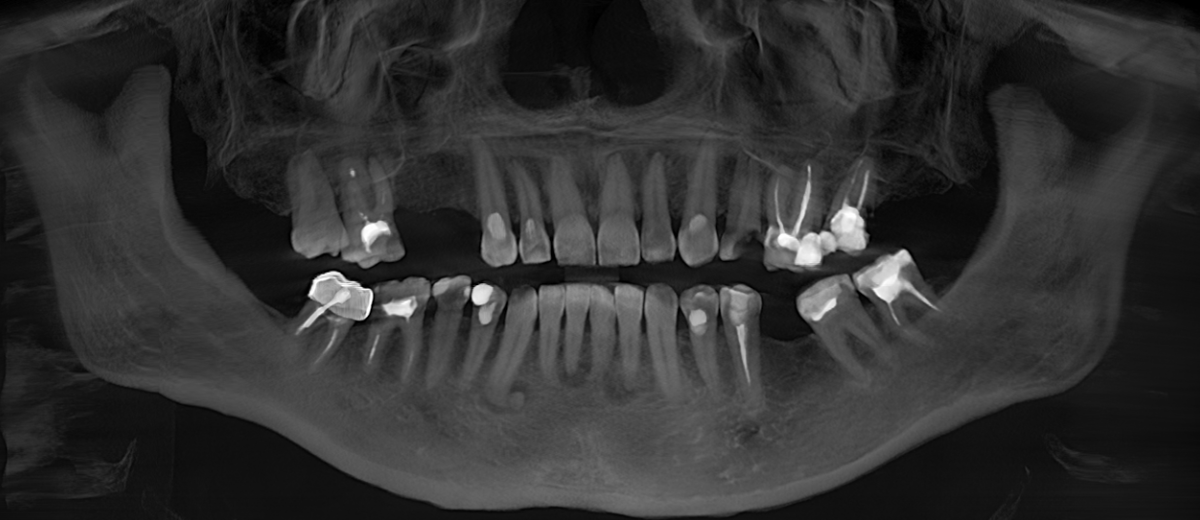

Ниже панорамный снимок, где хорошо видно, как из-за длительного (овер 10 лет) отсутствия 6-го зуба на нижней челюсти слева (на снимке справа) соседние зубы – седьмой и восьмой – наклонились в сторону отсутствующего.